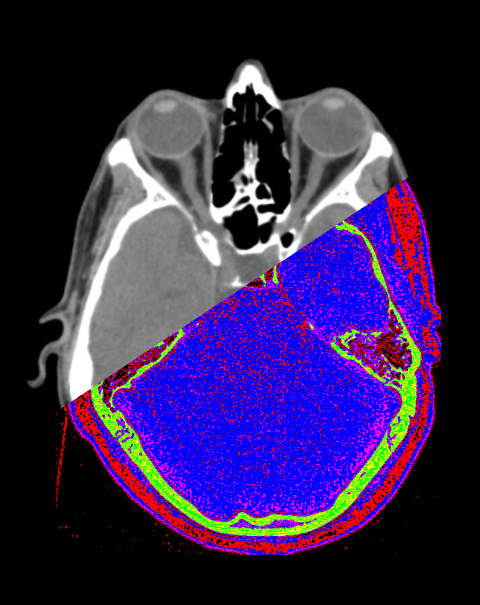

- Axial, sagittal and coronal Images without exceeding 3mm slice thickness, reformatted in soft-tissue (WW: 400, WL: 40) and bone window (WW: 4500, WL: 450).

Explanation: for the evaluation of foreign bodies in orbital area, reformation slice thickness should not exceed 1.5mm.